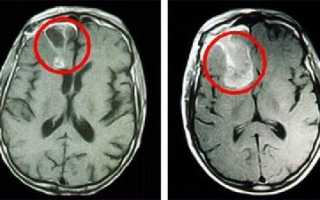

Наилучшими способами объективного выявления опухоли полушарий мозга признаны методы нейровизуализации: КТ и МРТ головного мозга. Они позволяют определить точную локализацию опухоли полушарий мозга и дифференцировать ее от внутримозговой гематомы, кисты при сирингомиелии, абсцесса головного мозга, рассеянного склероза, эпилепсии. Однако поставить достоверный диагноз и верифицировать опухоли полушарий мозга позволяет лишь гистологическое исследование. Оно может проводится с образцами мозговой ткани, полученными в ходе стереотаксической биопсии или интраоперационно.

Для адекватной оценки глиомы головного мозга пациента направляют на магниторезонансную томографию. Именно этот вид диагностики позволяет точным образом в трехмерном изображении определить местоположение опухоли, ее объем и зону поражения.

Магнитно-резонансная томография (мрт) при глиобластоме

МРТ позволяет с высокой степенью уверенности говорить о диагнозе мультиформной глиобластомы и широко используется для определения местоположения и размера опухолей мозга. Фактически, этот метод имеет наивысшую степень достоверности среди других лучевых методов. Некоторые другие процессы, в основном объёмные образования с геморрагическим компонентом, могут имитировать мультиформную глиобластому на МРТ, включая абсцессы мозга и инфаркты. В случае неясной или спорной МРТ-картины может быть полезной экспертная оценка МРТ специализированными радиологами.

Как выглядит глиобластома на МРТ? Как правило, образование на томограммах представляет собой зону, имеющую в основном пониженный сигнал на Т1-взвешенных изображниях и повышенный сигнал на Т2- взвешенных изображениях. Могут присутствовать внутренние кистозные участки, участки потери сигнала, обусловленные крупными сосудами, внутренние зоны повышенной интенсивности сигнала на Т1-ВИ (геморрагические очаги), новообразованные сосуды, очаги некроза, обширный перитуморозный вазогенный отеком и значительный масс-эффект. Также может выявляться неравномерное, но интенсивное накопление контрастного вещества на основе гадолиния (та же картина наблюдается на КТ после введения йодсодержащего контраста), как в основной опухоли, так и в метастатических очагах, характерных для МФГ. МРТ более чувствительна к этим изменениям, чем КТ.